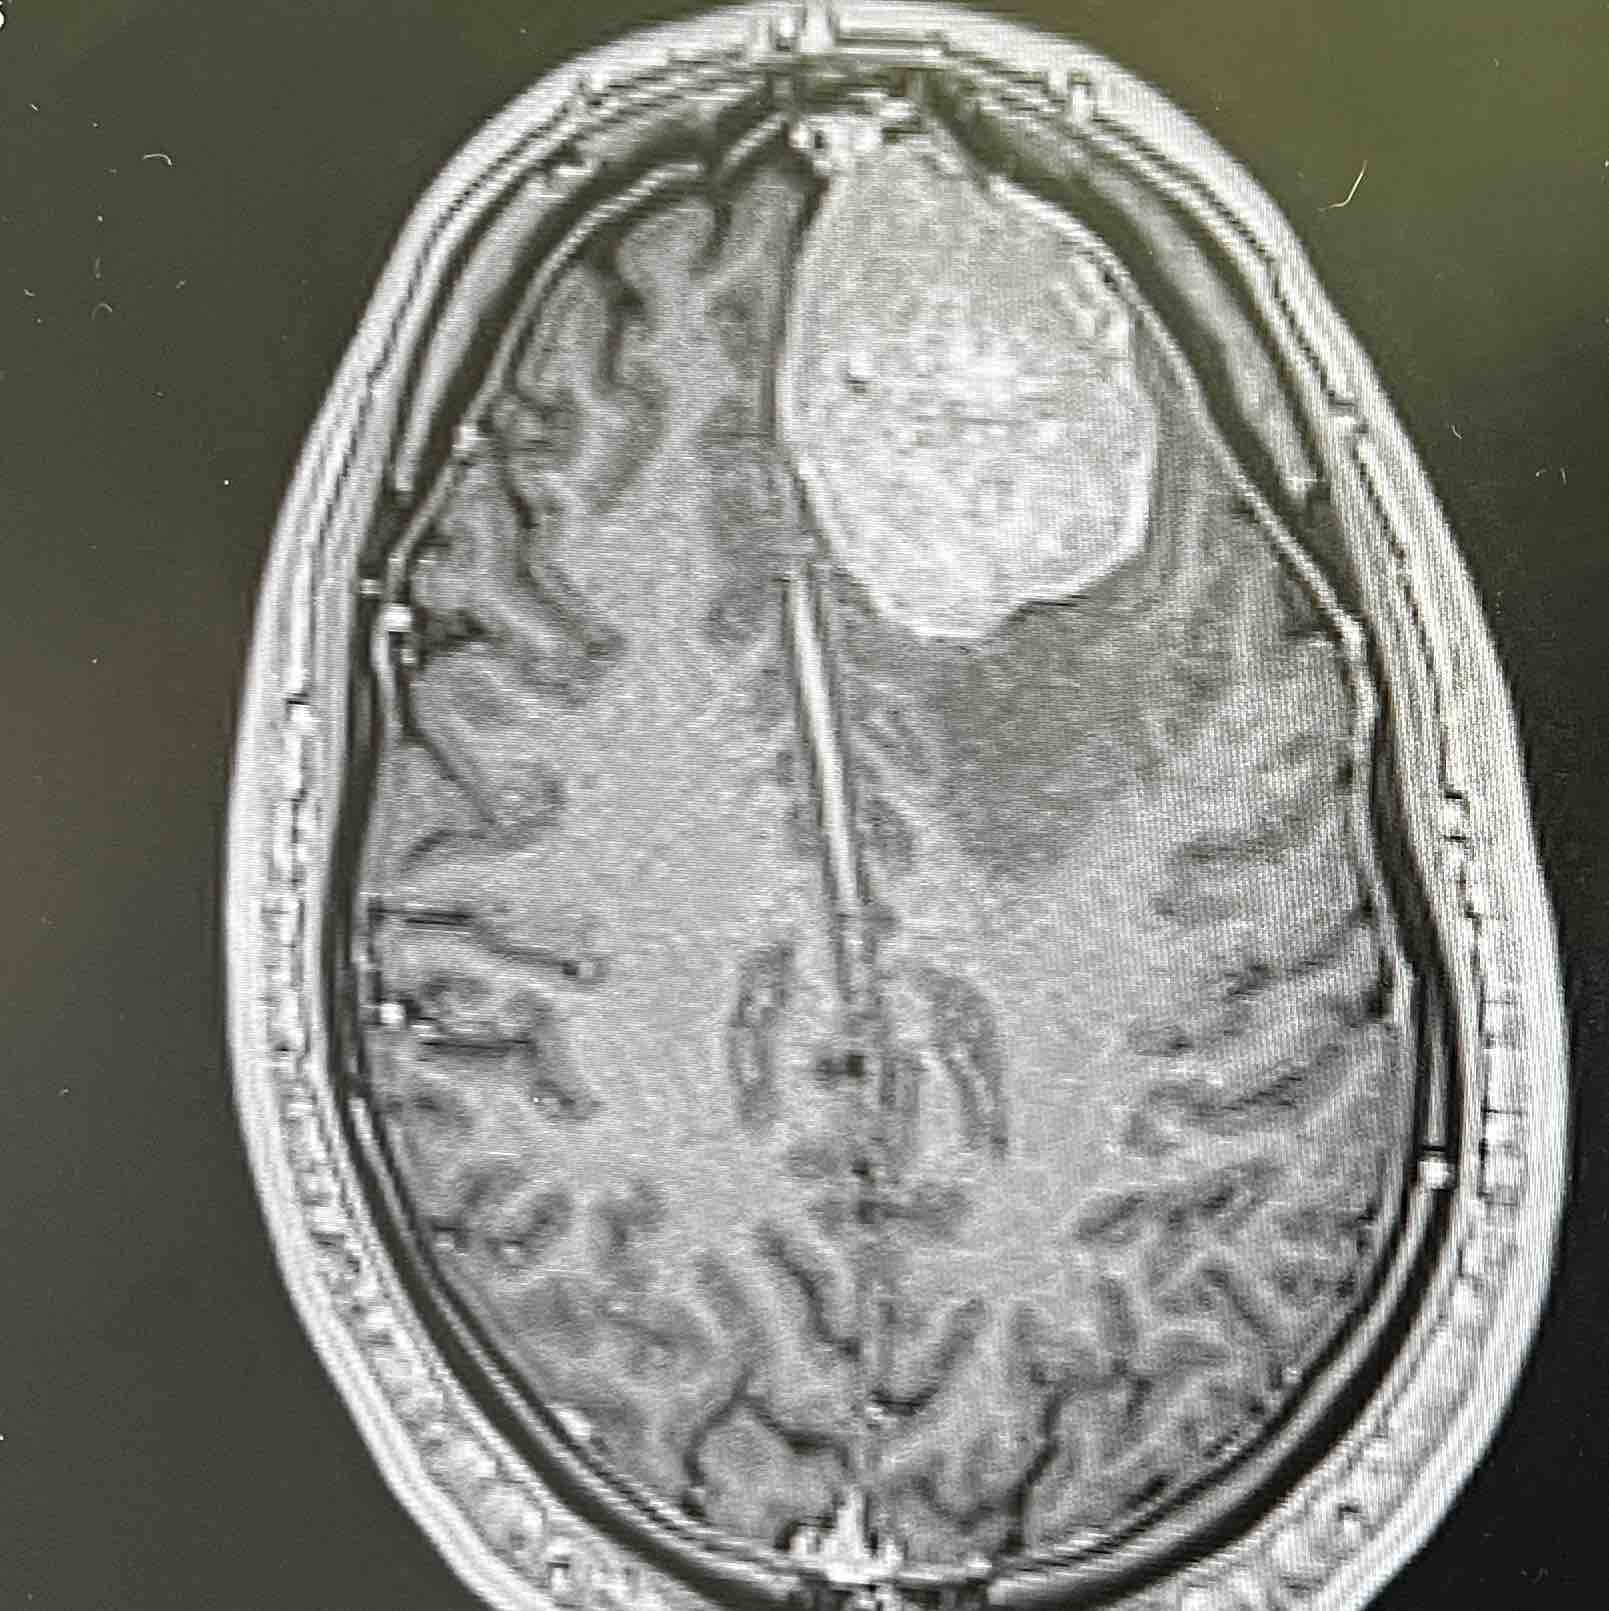

As part of my ongoing care, I have met with my medical team to establish a long-term monitoring plan. The tumor resection was successful, and biopsy results confirmed a WHO grade 2 atypical tumor. Since there is a risk of recurrence, I will continue to be monitored closely with regular MRIs over the next 1–2 years. I will also remain on anti-seizure medication for at least the next year.

I have been to the neurologist who advised I’ll need to continue monitoring by MRI for the next 1-2 years.

They advised that the tumor resection was successful and that the biopsy results came back as a WHO grade 2 atypical tumor.

The chances of it reforming is why they will be monitoring by MRI.

Surgery recently took place on 2/17/2025 and 2/18/2025.